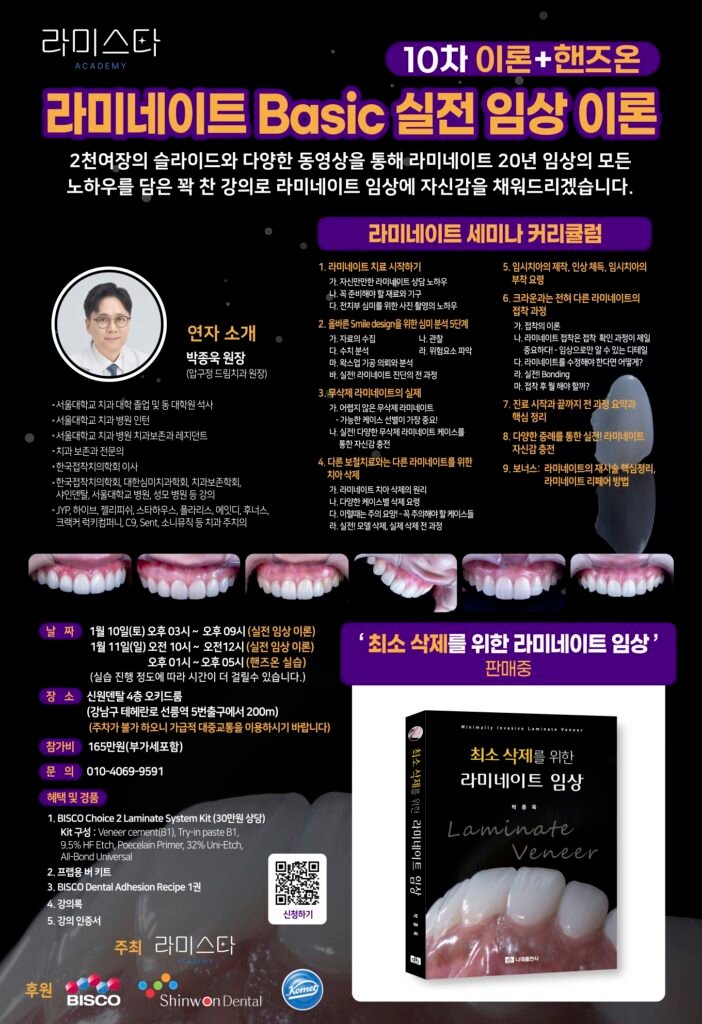

드림치과 박종욱 원장의 27년 임상 경험이 담긴 최소삭제 라미네이트(Minimal-prep Laminate Veneer) 치료 과정을 소개합니다.

드림치과는 2006년부터 압구정에서

최소삭제·자연스러운 라미네이트만을 전문으로 진료해왔습니다.

27년 경력의 박종욱 원장이 직접 진단·시술하며